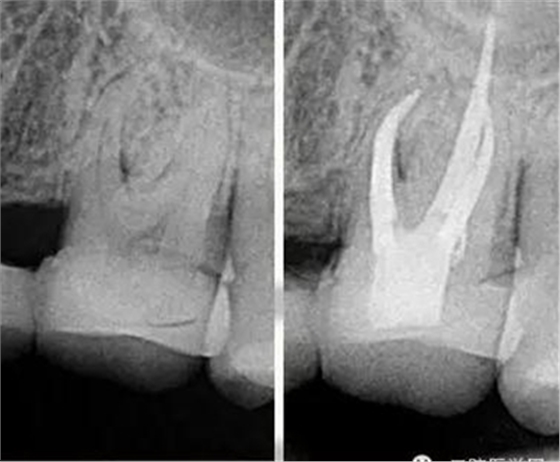

我喜歡比較有挑戰(zhàn)的工作,在牙科治療中最有挑戰(zhàn)的治療之一就是根管治療。牙齒的根管系統(tǒng)非常復(fù)雜,就像一顆大樹,有主干也有枝葉,要把這么復(fù)雜的根管系統(tǒng)治療到位很有挑戰(zhàn)。它需要掌握的技術(shù)比較多,涉及到的器械是最多的,治療一顆牙常常需要擺出3大桌的工具。當(dāng)你花了很長時間把一顆牙的根管治療治療到位以后,看著術(shù)后的X線片,感覺就像在欣賞一件藝術(shù)作品,非常美,非常有成就感。

把根管感染清理出來,除了旋轉(zhuǎn)鎳鈦器械的切屑往外帶出來以外還有一些殘留的碎屑粘在根管壁上,要把這部分碎屑沖出來,就會用到根管超聲器械或者聲波器械,通過高頻震動,帶動根管內(nèi)部沖洗液的震動,從而讓那些殘留碎屑從根管壁上脫落下來并且被沖出來。好了,現(xiàn)在根管內(nèi)部都清理干凈了,剩下這個空腔我們要把它完全的填起來,不讓外界的細(xì)菌進(jìn)入內(nèi)部。這個時候我們會用到一種材料叫牙膠,這種材料比較穩(wěn)定,可以長期的存在根管里?,F(xiàn)在比較先進(jìn)的牙膠充填是熱牙膠充填系統(tǒng),把牙膠加熱到一定溫度后具有流動性,通過垂直加壓,讓它自動的把整個根管系統(tǒng)都填滿。